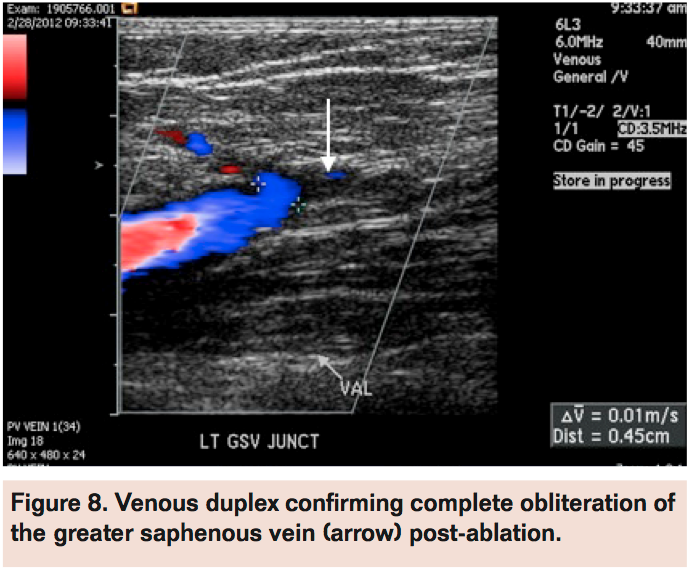

Angiogram of the left common femoral artery with runoff revealed distal left superficial femoral artery occlusion (Figure 1A) with reconstitution of the distal popliteal artery and 2-vessel runoff into the left foot via the anterior tibial and peroneal arteries (Figure 1B). Revascularization of the occlusion was performed using balloon angioplasty and stent placement (Figure 2A) with good angiographic result and runoff (Figure 2B). She had complete resolution of her claudication symptoms, but returned 1 year later with ulceration of the medial aspect of her left foot above the medial malleolus. Repeat angiogram revealed restenosis of the stent (Figure 3A) and re-occlusive disease of the distal popliteal artery stent extending into the anterior tibial artery (Figure 3B) requiring atherectomy and balloon angioplasty for successful revascularization (Figure 4). However, her ulceration progressed despite revascularization, prompting further evaluation of the etiology of her ulcer (Figure 5). A venous Doppler study of the left lower extremity revealed severe reflux of the left greater saphenous vein (Figure 6) with flow above baseline in the proximal, mid, and distal portions of up to 1.7 seconds. An incompetent perforating vein was also noted in the left calf 23 cm from the ankle and measured at 0.33 cm in diameter (Figure 7). She subsequently underwent radiofrequency ablation of the left greater saphenous vein followed by the left calf perforator with complete occlusion by ultrasound (Figure 8).